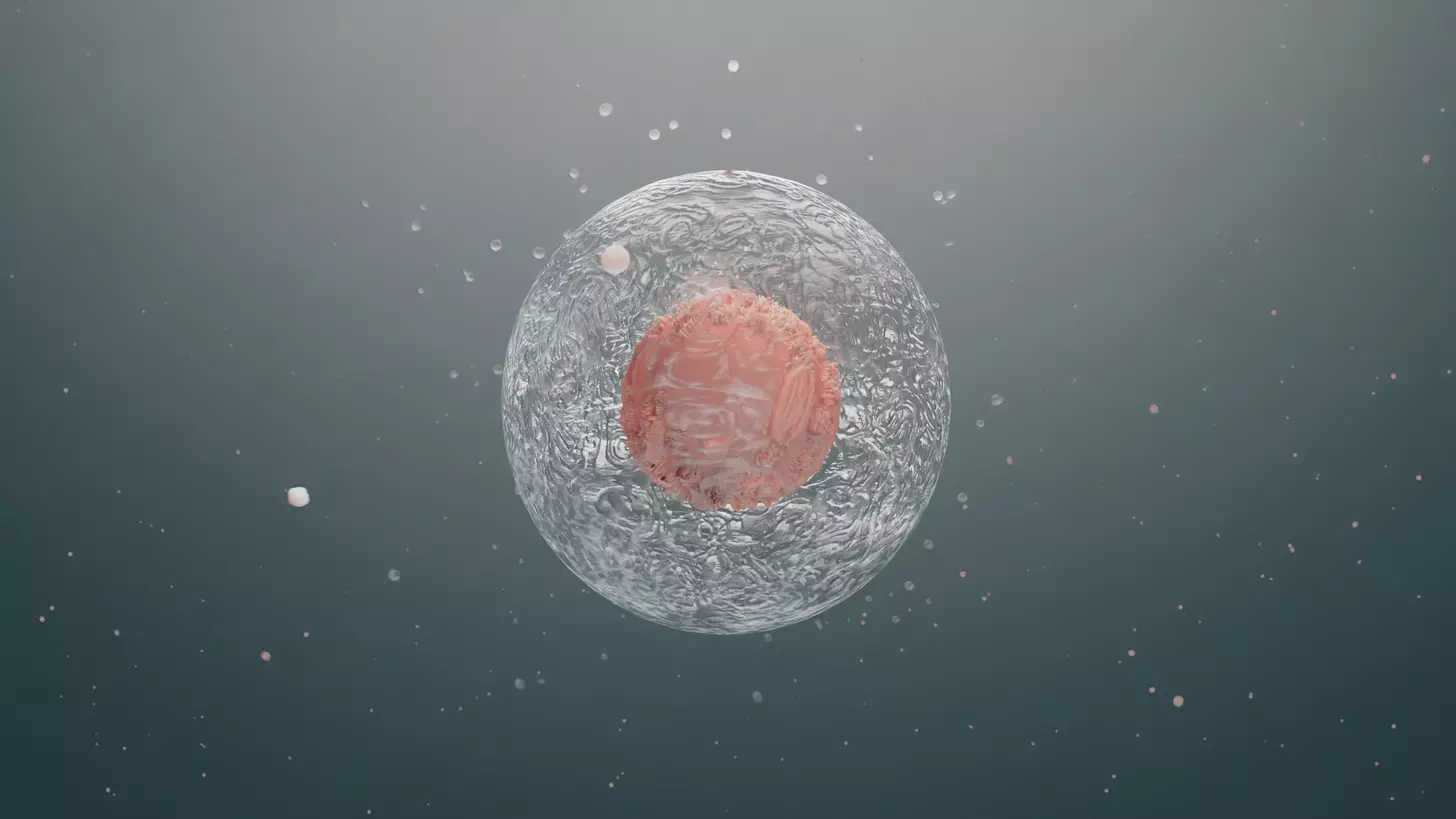

Structural and Molecular Characteristics of B Cells

B cells, or B lymphocytes, are key players in the adaptive immune system. They have special features that help them fight off infections. These include making antibodies and showing antigens to T cells.

Morphological Features and Cellular Organization

B cells are round and about 7-12 micrometers in size. They have a big nucleus and a small amount of cytoplasm. This shows they are very active in making proteins and dividing.

The cytoplasm of B cells has important organelles like the endoplasmic reticulum and Golgi apparatus. These help in making and sending out antibodies. This highlights their role in fighting infections.